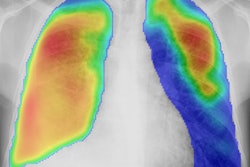

After observing U.K. radiographers at work, the multicenter research team found that many radiographers were using the cropping feature available with DR software to adjust images after they were exposed to make them look better, rather than positioning patients properly within the x-ray beam and using correct collimation settings (JMIRS, Vol. 50:2, pp. 234-242).

The observers noted frequent use of digital image cropping after acquisition, according to the research team, with some radiographers cropping as little as 1 cm and others cropping as much as 5 cm. When asked why in interviews, many radiographers said they resorted to cropping to produce images that were "neat" and "tidy," and in some cases to compensate for overcollimation.

The researchers postulated that the radiographers were trying to meet the ideal conception of an aesthetically pleasing x-ray image and that they were tempted to "open up" collimation during image acquisition and then crop down afterward -- a classic definition of collimation creep.